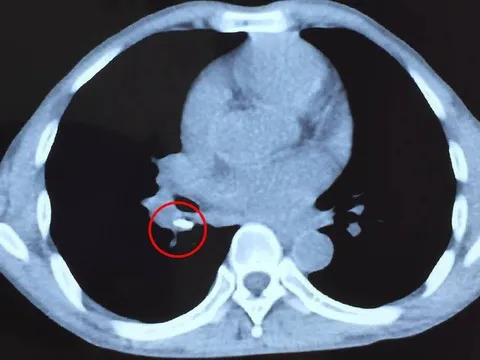

VTV.vn - Bệnh viện Đa khoa khu vực Quảng Nam vừa tiếp nhận nam bệnh nhân (49 tuổi, trú tại Điện Bàn, Quảng Nam) bị phản vệ độ III do tự ý uống kháng sinh tại nhà.